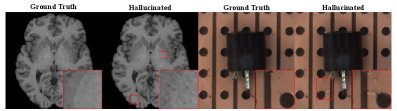

Figure 3 shows intrinsic and extrinsic hallucinations generated by HalluGen. The images appear realistic, altering tissue morphology such as sulci and ventricles. A key trend emerges: intrinsic hallucinations often cause morphological distortions (shape or size), whereas extrinsic ones introduce new plausible structures, leading to topological changes.

We assess perceptual realism using FID and semantic deviation via tissue segmentation IoU within hallucinated regions. Since no prior work addresses hallucination generation for image restoration, we compare HalluGen against three baselines: (1) vanilla DPS [chung2023diffusion] as a non-hallucinated reference, (2) random rotation in selected patches, and (3) measurement perturbation by adding noise in measurement space (e.g., the original input image). We additionally evaluate HalluGen with different feature extractors. Gaussian Mixture Models are used for segmenting gray matter, white matter, and CSF.

Table 1 shows HalluGen achieves FID comparable to DPS, while segmentation IoU drops by 50% within hallucinated regions, indicating strong semantic deviation. Although random rotations and measurement perturbations yield low FID, they apply only to intrinsic cases and introduce patch artifacts. HalluGen performs consistently across different feature extractors; additional visuals are provided in the supplementary. An expert study (n=2), where HalluGen outputs were mixed with vanilla DPS reconstructions, yielded only 50.5% identification accuracy, confirming that HalluGen produces visually realistic hallucinations.

We validate HalluGen’s taxonomy compliance in Tab. 2 by measuring measurement- and image-space deviations within masked regions. Intrinsic hallucinations exhibit measurement loss roughly 7 times higher than DPS, confirming violation of measurement consistency. Extrinsic hallucinations retain low measurement loss but diverge in image space, consistent with the formal taxonomy (Eq. 2–3). Fig. 3 further visualizes measurement-space difference maps, with extrinsic cases showing much lower errors than intrinsic ones within hallucinated regions.